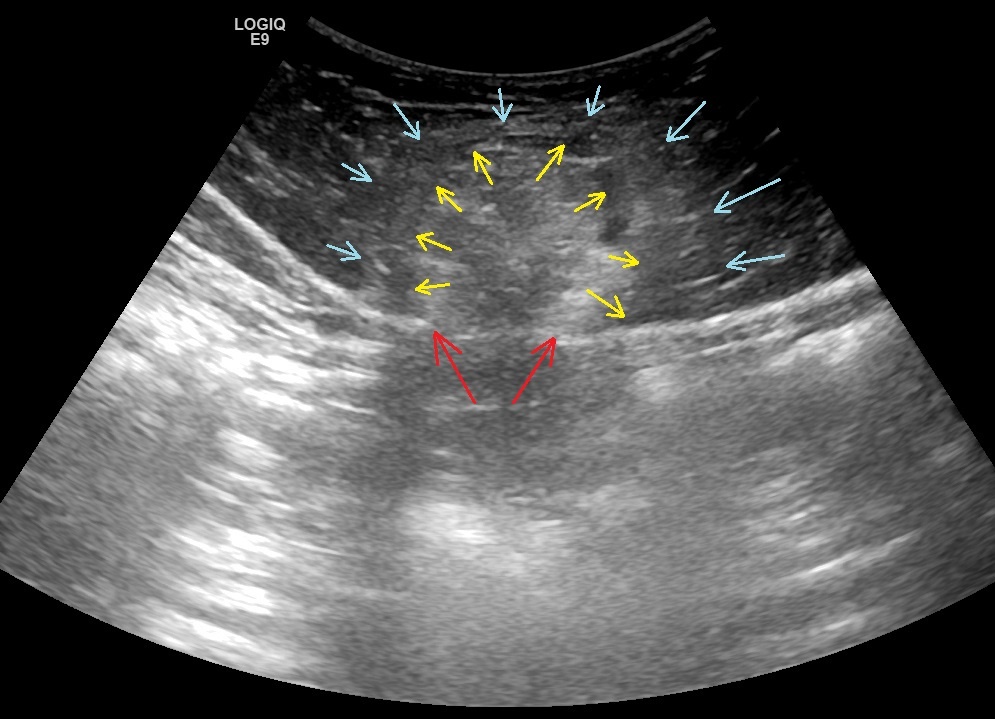

Вначале исследование проводилось конвексным датчиком. Выявлено грыжевое образование в надчревной области размерами 45х33х40 мм, состоящее из жировой ткани (фрагмент сальника). Было отмечено наличие нечеткости контуров грыжевого образования за счет зоны воспалительной инфильтрации в прилегающей жировой ткани.

Рис. 01. Жиросодержащая грыжа передней брюшной стенки. Красными стрелками указаны грыжевые ворота. Желтые стрелки - контуры скопления жировой ткани сальника в составе грыжевого содержимого. Голубые стрелки - зона инфильтрации подкожной клетчатки.